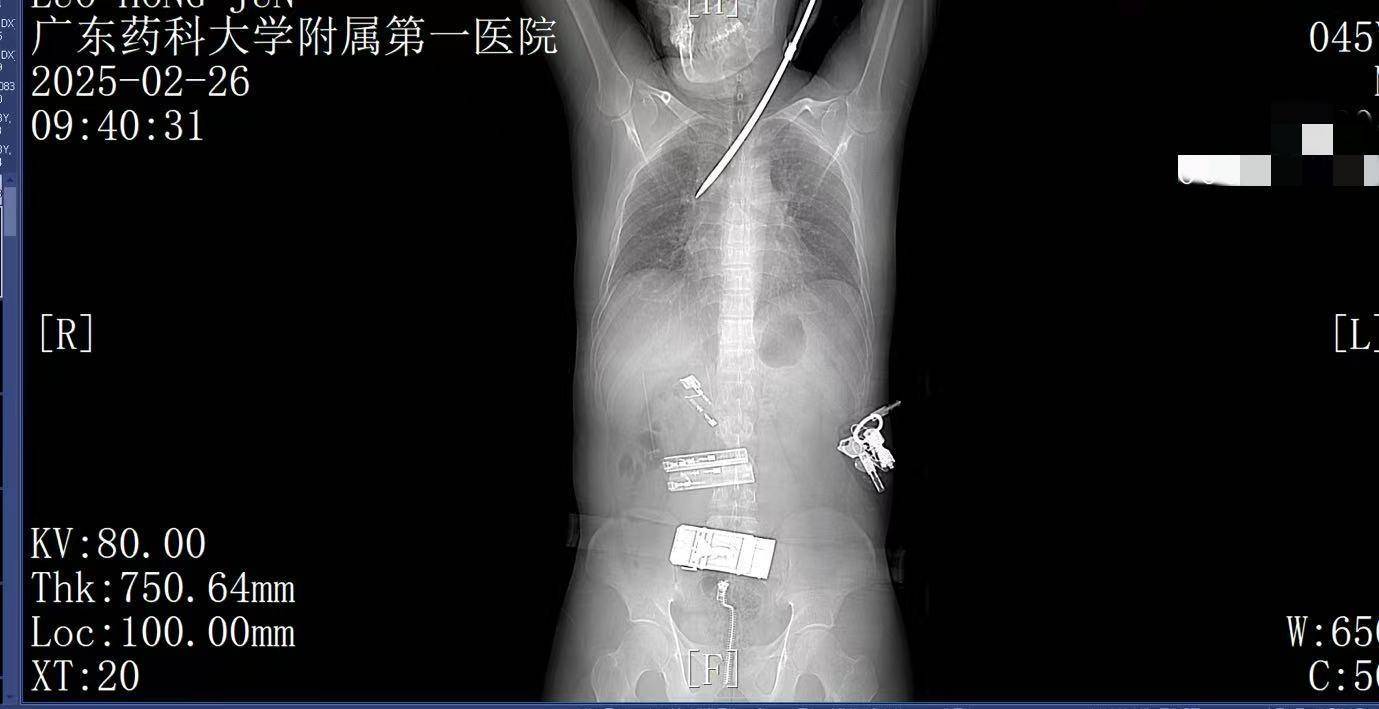

2月26日上午9时许,44岁的电梯工人罗师傅(化姓)正在广州某工地弯腰工作,突然一把螺丝刀从20多米高处坠落,刺中罗师傅的胸背部。罗师傅当即疼痛难忍,呼吸困难。工友立即呼叫120。一场惊心动魄的生死救援立即展开。

9:22,广东药科大学附属第一医院救护车到达现场,查看患者伤情后,黄业君主治医师立即固定好螺丝刀,避免再次移动损伤神经血管,并马上电话联系医院后方,医院急诊科主任曾育辉立即通知心胸外科、脊柱外科等相关科室紧急会诊。

9:39,救护车到达医院大门,院内急救团队已经做好准备。在紧密监护的情况下,全程采用绿色通道。到达医院时,罗师傅已经面色苍白,呼吸急促。螺丝刀已深深刺入罗师傅右肺,随时可能因大出血而危及生命。

9:41,快速完成头+胸+腹部CT检查,经多学科会诊,明确螺丝刀异物刺入肺部。CT显示螺丝刀紧贴肋间血管、上肺后段动脉,尖端距右肺门仅2厘米,一旦贸然拔出螺丝刀,极有可能引发大出血,导致失血性休克甚至死亡,必须紧急手术。